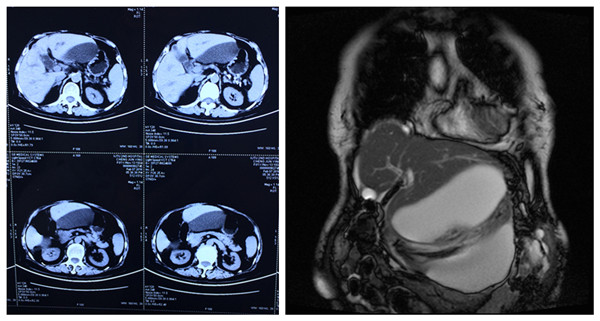

消化内科完成一例经胃壁胰腺假囊肿金属支架引流术,患者系高龄胆总管结石合并胰腺炎患者,并且胰腺炎反复发作并发巨大假性囊肿,腹腔脏器受压迫,引起肠道梗阻以及肾脏血管受压迫,多学科会诊后认为在行进一步治疗前,必须首先解决胰腺假性囊肿压迫问题。经多方协调,在放射科介入手术室的大力配合下,消化内科王进海主任与戴社教教授的指导,由消化内科马师洋主治医师与宋亚华主管护师进行手术操作,在超声内镜与DSA的引导下顺利完成假囊肿穿刺、扩张以及金属对吻支架释放,术后患者腹腔压力明显恢复正常,为后续治疗创造了良好的条件,这是我院首例采用这种特殊支架进行胰腺假囊肿治疗,在国内处于领先水平。

术前